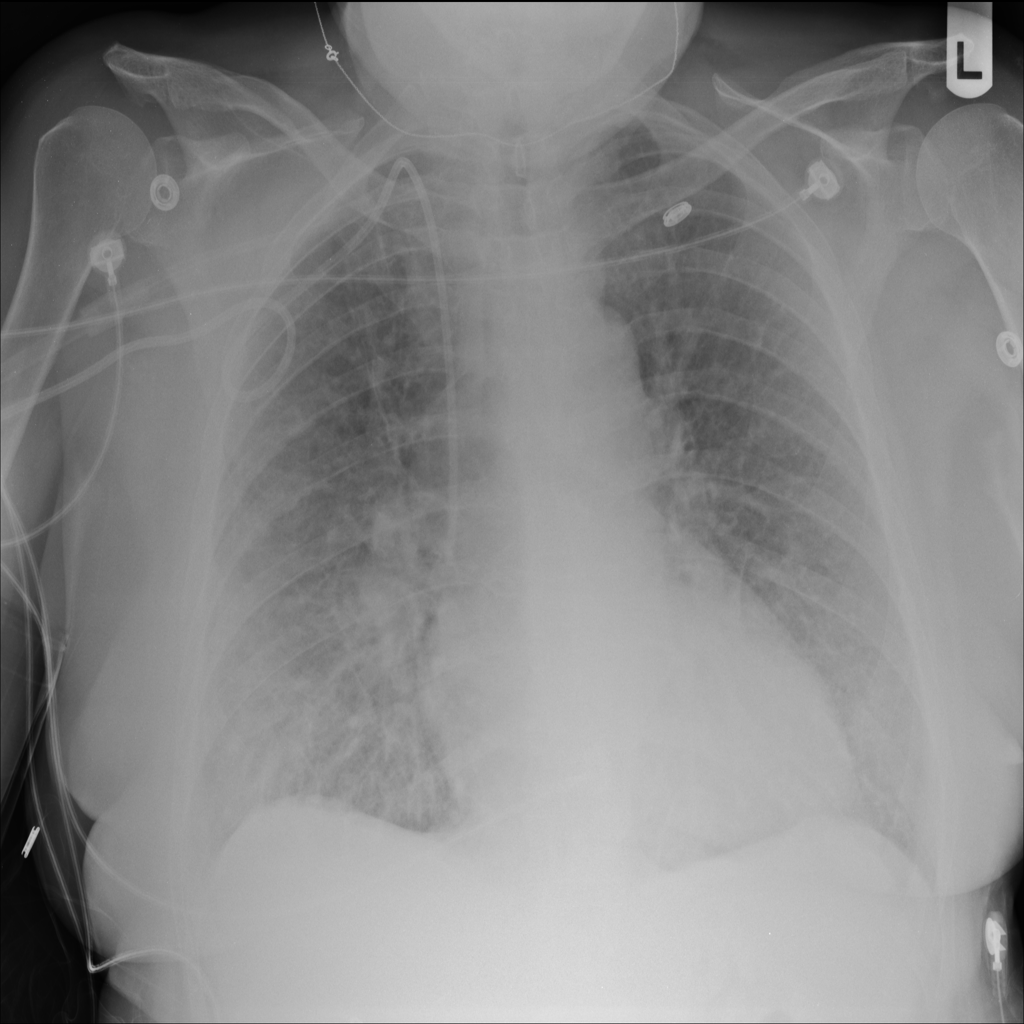

PAT-24D9 · IMG-006Edema

PAT-24D9 · IMG-006

AP